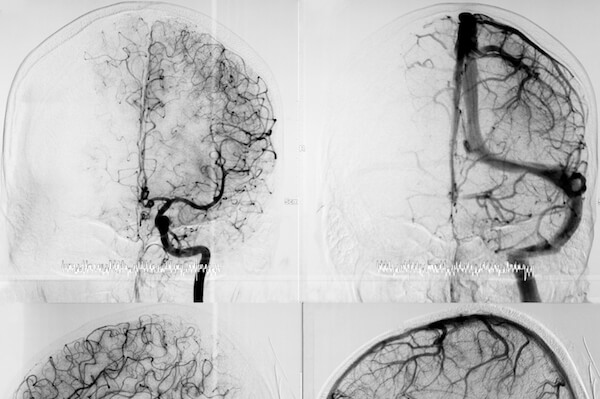

- embolization of cerebral aneurysms through coiling technique or flow diverter implant

- embolization of AVMs (arteriovenous malformations), AVFs (arteriovenous fistulas) or dAVFs (dural arteriovenous fistulas, or fistulas localized in the dura layers)

The femoral artery is accessed through catheters that have the task of engaging the aortic arch and subsequently the epiaortic vessels, until they reach the site to be treated.

Once the target is reached, other devices such as microcoils, stents or embolizing agents are inserted, depending on the pathology.